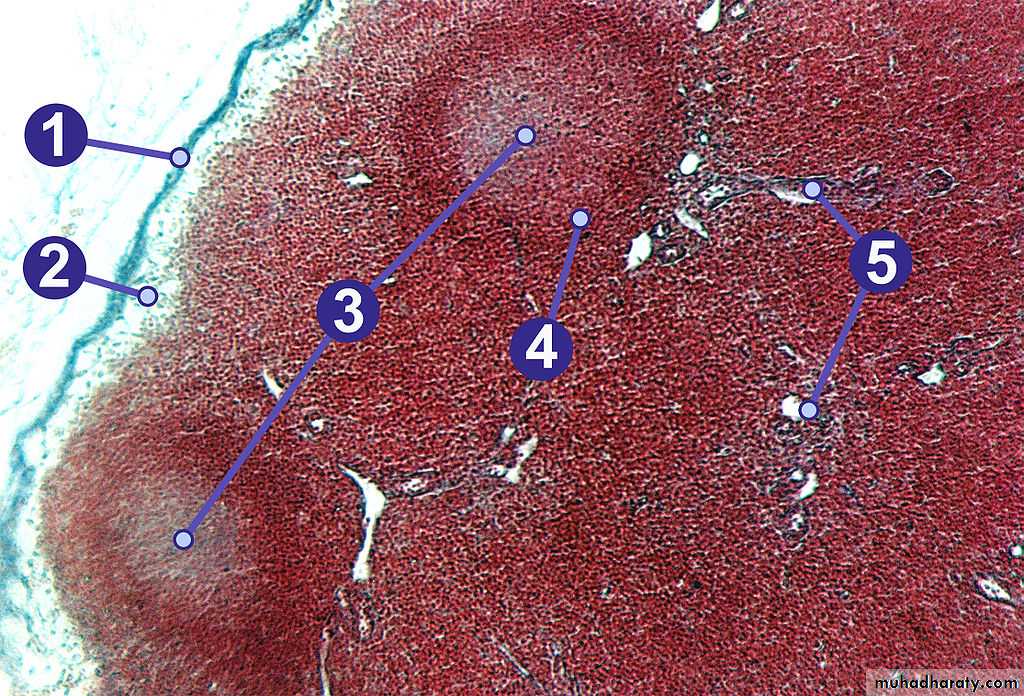

(Fig. 6): Section through a lymph node. 1) Capsule; 2) Subcapsular sinus; 3) Germinal centre; 4) Lymphoid nodule; 5) Trabeculae.